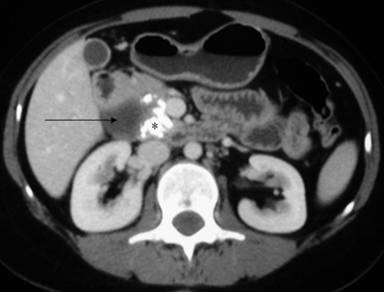

A 27-year-old female presented with a history, since childhood, of recurrent dull non-radiating upper abdominal pain, usually lasting for 2-3 days, occurring every 2-3 months and relieved with pain medications. She had been taking proton pump inhibitors, prokinetic agents and enzyme supplements for the previous 4 years. The current attack of abdominal pain was accompanied by fever and jaundice. Her total bilirubin was 14 mg/dL (reference range: 0.2-1.0 mg/dL), AST 100 IU/L (reference range: 15-48 IU/L), ALT 150 IU/L (reference range: 10-40 IU/L) and alkaline phosphatase was 280 IU/L (reference range: 40-120 IU/L). A computed tomography (CT) scan revealed a type I choledochal cyst with calcifications in the uncinate process of the pancreas (Figure 1). She had undergone common bile duct stent placement for her symptoms elsewhere but without relief of pain. Magnetic resonance cholangiopancreatography (MRCP) revealed calcifications in the region of the uncinate process of the pancreas, the presence of a type I choledochal cyst with dilatation of the right and left hepatic ducts at their confluence suggesting an anomalous pancreaticobiliary ductal junction with a common bile duct stent in place (Figure 2). There were no symptoms of endocrine or exocrine dysfunction and no pancreatic pain. She was referred to us for surgical consultation. Preoperatively, her total bilirubin had dropped to 1.7 mg/dL (direct 0.7 mg/dL; reference range: 0-0.2 mg/dL), ALT 16 IU/L, AST 31 IU/L, alkaline phosphatase 65 IU/L, gamma glutaryl transpeptidase (GGT) 31 IU/L (reference range: 0-60 IU/L); serum amylase and coagulation profiles were within normal limits. She underwent choledochal cyst excision with a Roux-en-Y hepaticojejunostomy. The procedure was uneventful. She has since been treated conservatively twice for symptoms of adhesive small bowel obstruction but has been asymptomatic for her primary disease during a follow-up period of 4 years.

Figure 1. Contrast-enhanced CT showing the lower end of the choledochal cyst (arrow) with calcification (*) at the uncinate process of the pancreas. |